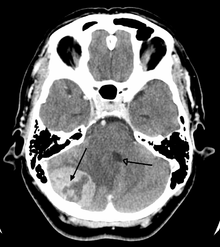

Medical imaging plays a central role in the diagnosis of brain tumors. Early imaging methods—invasive and sometimes dangerous— such as pneumoencephalography and cerebral angiography have been abandoned in favor of non-invasive, high-resolution techniques, especially magnetic resonance imaging (MRI) and computed tomography (CT) scans. Neoplasms will often show as differently colored masses (also referred to as processes) in CT or MRI results.

- Benign brain tumors often show up as hypodense (darker than brain tissue) mass lesions on CT scans. On MRI, they appear either hypodense or isointense (same intensity as brain tissue) on T1-weighted scans, or hyperintense (brighter than brain tissue) on T2-weighted MRI, although the appearance is variable.

- Contrast agent uptake, sometimes in characteristic patterns, can be demonstrated on either CT or MRI scans in most malignant primary and metastatic brain tumors.

- Pressure areas where the brain tissue has been compressed by a tumor also appear hyperintense on T2-weighted scans and might indicate the presence a diffuse neoplasm due to an unclear outline. Swelling around the tumor known as peritumoral edema can also show a similar result.

This is because these tumors disrupt the normal functioning of the BBB and lead to an increase in its permeability. However, it is not possible to diagnose high- versus low-grade gliomas based on enhancement pattern alone.